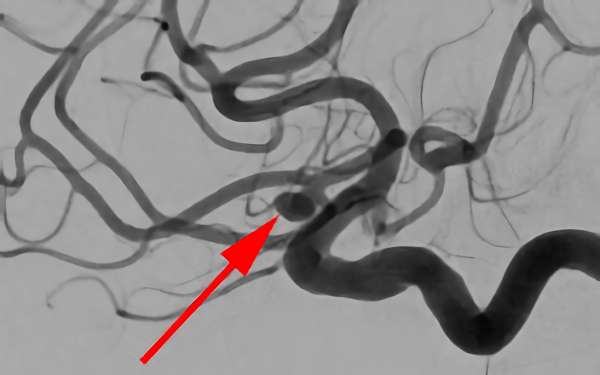

No.1627 手術前